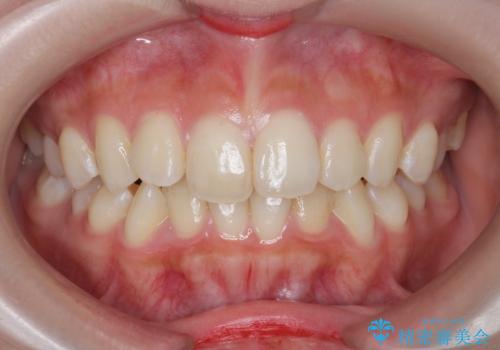

インビザラインライトで行う短期マウスピース矯正治療

- 前歯のガタつきを並べたいたいと、矯正治療を希望され来院されました。

とにかく短期間で前歯だけの治療を行いという希望が強く、全体矯正と前歯だけの部分矯正の仕上がりのイメージを確認したのち14枚のマウスピースで前歯のみの矯正治療を行っていくこととしました。

インビザラインライトは軽度なガタつきや傾斜の改善に用いられる全14枚のマウスピース矯正です。

短期間で治療の終了が見込めるだけでなく、料金もインビザラインフルに比べリーズナブルです。